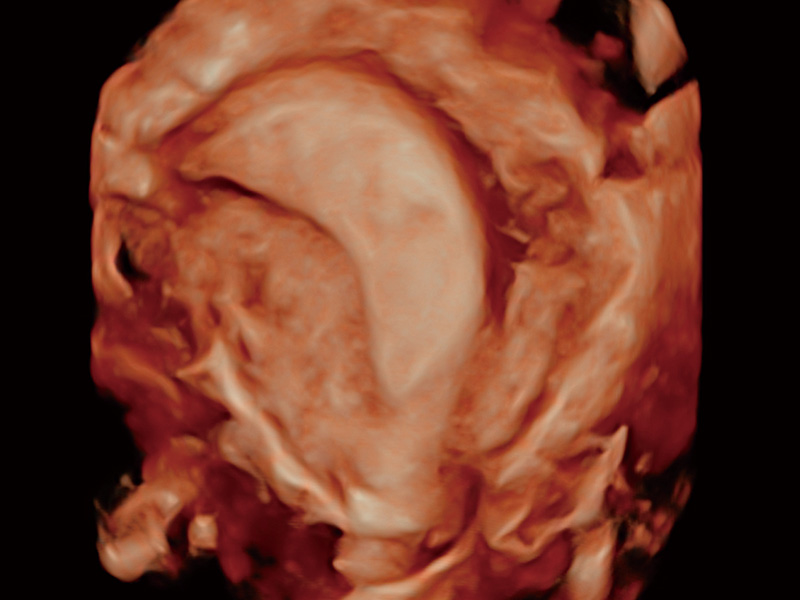

超声引导下胚胎移植